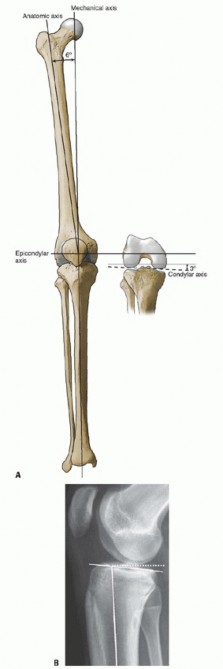

P ITFALLS Correct rotational positioning of the femoral and tibial components is a prerequisite for a success…

DEFINITION Total knee arthroplasty (TKA) is a successful surgical procedure that provides excellent and durab…

P ITFALLS Results of each type of alignment are technique dependent, and familiarity with each will reduce co…